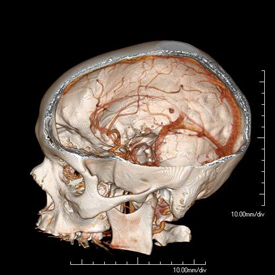

Diagnostic Radiology skull reconstruction

CTA of the Head and Neck image A for Radiology

How it works: CT angiography (CTA) evaluates the major vessels of the head, neck or both. An iodine based contrast agent is rapidly injected through an IV placed in a vein, usually in the arm. A CT scan uses x-rays to acquired images as the contrast bolus passes through the arteries. The data can then be reviewed in multiple planes, and 3 dimensional images can also be created for review.

Benefits: CT angiography is a fast and minimally invasive method of evaluating vessels for abnormalities such as narrowing, blockage, aneurysms, and other vascular malformations.